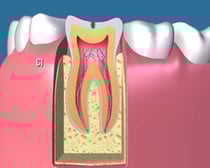

C3:

かなり虫歯が進行してしまって、歯の神経と呼ばれる歯髄にまで虫歯が達してしまった状態です。熱い物で痛みが出たり、場合によってはひどくズキズキ痛むことも少なくありません。

この場合、歯を大きく削って歯の神経を除去する難易度の高い根管治療や大きく歯を削ってすっぽりかぶせる治療が必要になり、その後多くの場合はかぶせ物で修復することになります。